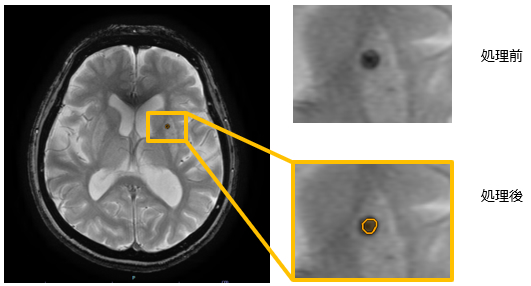

① 頭部FLAIR高信号強調フィルタ/T2低信号強調フィルタ

今回リリースする「頭部FLAIR高信号強調フィルタ」は、FLAIR画像から周辺組織と比較して高信号の領域を抽出する機能である。一般的に、頭部FLAIR画像で高信号となる領域は白質病変や多発性硬化症、浮腫であることが多く、本機能により、これらの所見の診断支援に繋がることが期待される。

「頭部T2低信号強調フィルタ」は、T2強調画像から周辺組織と比較して低信号の領域を抽出する。

一般的に、頭部T2強調画像で低信号となる領域は出血であることが多く、本機能により微小出血の診断支援に繋がることが期待される。今回拡充する「脳区域ラベリング(MR)」機能の解剖情報を反映した所見文候補作成支援機能と併用することで、読影ワークフロー全体を支援する。